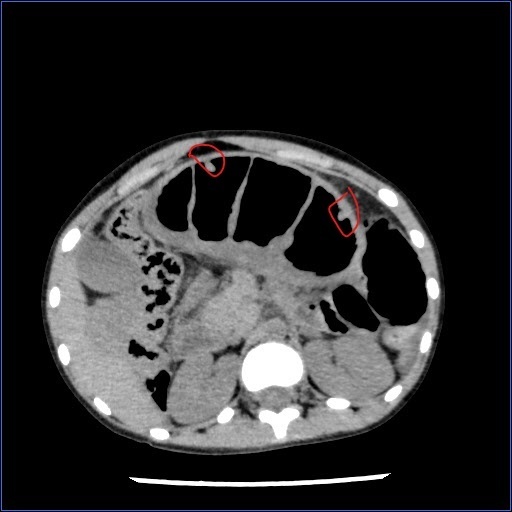

CT检查显示患者肠套叠和多发息肉。(图片由医院提供)

儿科、普外科及手术室紧密配合,迅速完成了术前准备,将患儿送到手术室。由杨俊杰副主任医生带领的手术团队迅速进行剖腹探查,发现患者近1米小肠套叠坏死,黏膜完全脱出,肠内容物均为黑色坏死组织。手术医生迅速减压后离断坏死小肠,并继续探查发现小肠多处息肉及一段套叠梗阻小肠,且经过复位后仍有梗阻,手术团队果断决定切除两段梗阻小肠并进行吻合,同时将触及的小肠息肉切除送检。